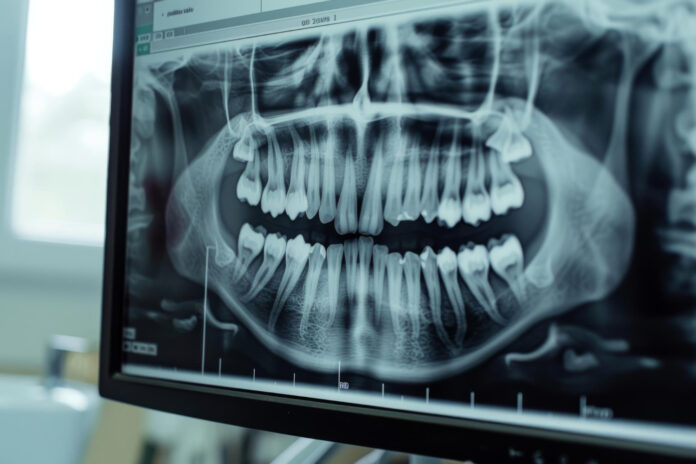

De acordo com a gerente de Serviços de Odontologia da SES, Francielle Gonçalves, a modernização dos equipamentos trará um impacto significativo na qualidade do atendimento. “Por exemplo, com a aquisição para os hospitais regionais do Gama [HRG] e de Taguatinga [HRT], será possível realizar radiografias panorâmicas, exames essenciais na odontologia, ampliando a capacidade de atendimento de pacientes, diagnóstico e tratamento nas unidades”, relata.

Entre os novos recursos, destaca-se o tomógrafo odontológico por feixe cônico, que oferece imagens em 3D, permitindo visualizar com precisão fraturas, problemas de canal e articulações. Segundo a gerente, “esse equipamento possibilita diagnósticos mais detalhados, principalmente na área de patologia, como na avaliação de lesões ósseas maxilomandibulares. As imagens tridimensionais revelam a topografia e extensão das lesões, além da relação com estruturas anatômicas importantes, o que é essencial para um planejamento cirúrgico adequado e acompanhamento pós-operatório”.

Com o novo tomógrafo, o Centro de Especialidades Odontológicas da 712/912 Sul se consolida como uma central de radiologia completa. Além de tomografia computadorizada, o local oferece radiografias panorâmicas e telerradiografias, com um aparelho que permite a realização de todas essas modalidades.